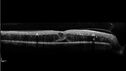

Siegrist Streaks and severe diabetic macular edema161 views56 year old female who presents four years after developing necrotizing fascitis and multiple organ failure from an infected foot from a roofing nail. Her vision was 20/100 OU. She has multiple peripheral pigment spots consistent with Siegrist streaks.Sep 19, 2023